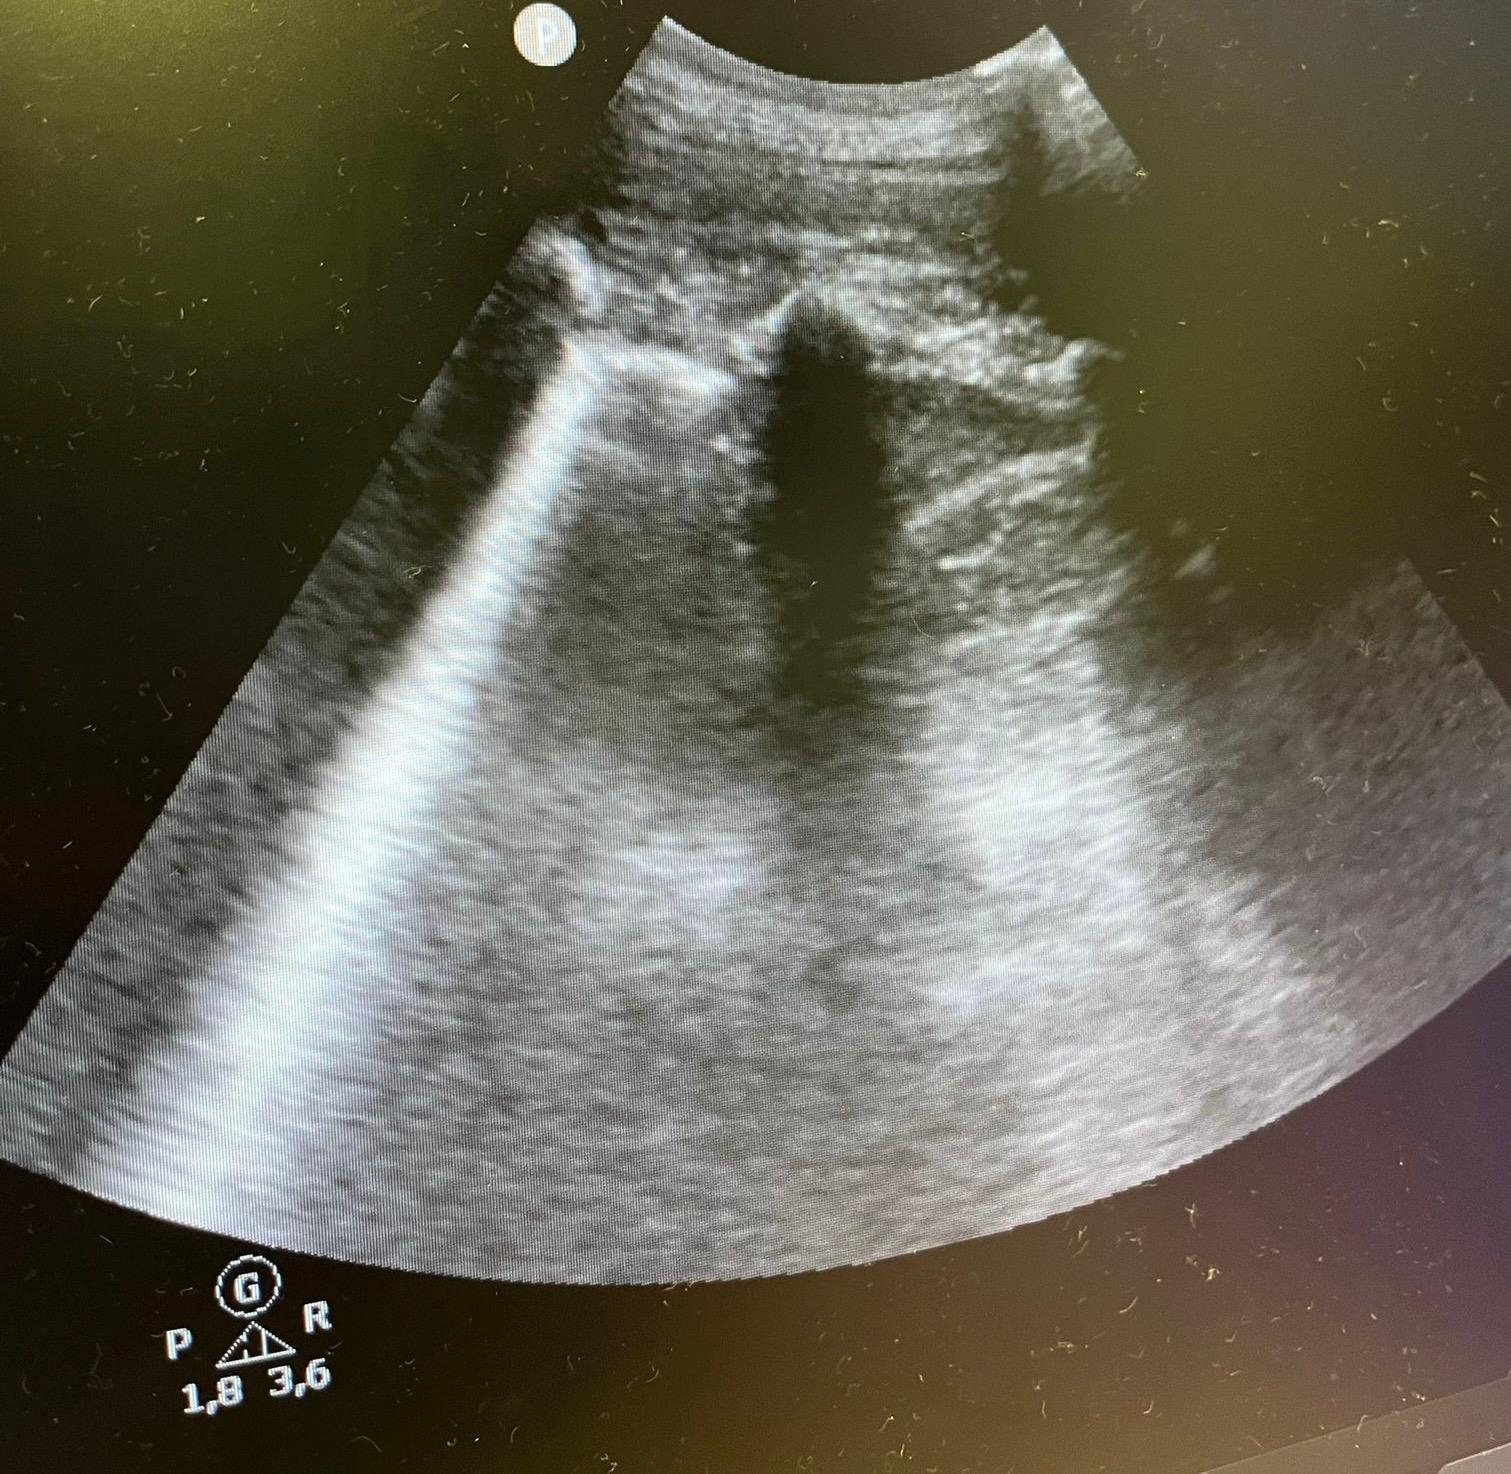

Juicio clínico: Se orienta como neumonía ya que el paciente cursa con fiebre y tiene una ecografía compatible; dado buen estado general del paciente y escalas FINE 35, CURB 65 de 0 se decide alta a domicilio con tratamiento oral.

En este caso podemos contemplar que nos es muy útil tanto en consultas de Atención Primaria como en Urgencias el uso de la ecografía como herramienta cuando tenemos dudas diagnósticas. El signo de la medusa es una imagen dinámica de la ecografía que se puede producir en caso de derrame pleural por una atelectasia compresiva, vemos una imagen similar a la de un brazo de medusa flotando en el contenido líquido. Conocer este signo puede ser de utilidad para sospechar un derrame pleural.